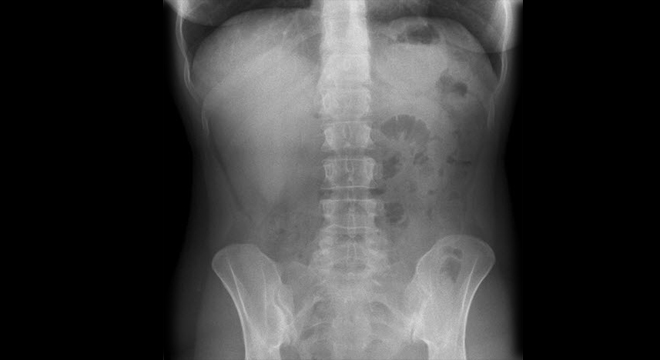

Verstopfung: Röntgenuntersuchung mit Kontrastmittel

Zur Diagnose einer Verstopfung werden verschiedene Untersuchungen und Abklärungen durchgeführt. Dazu gehören unter anderem:

• evtl. Röntgen mit Kontrastmittel und Luft